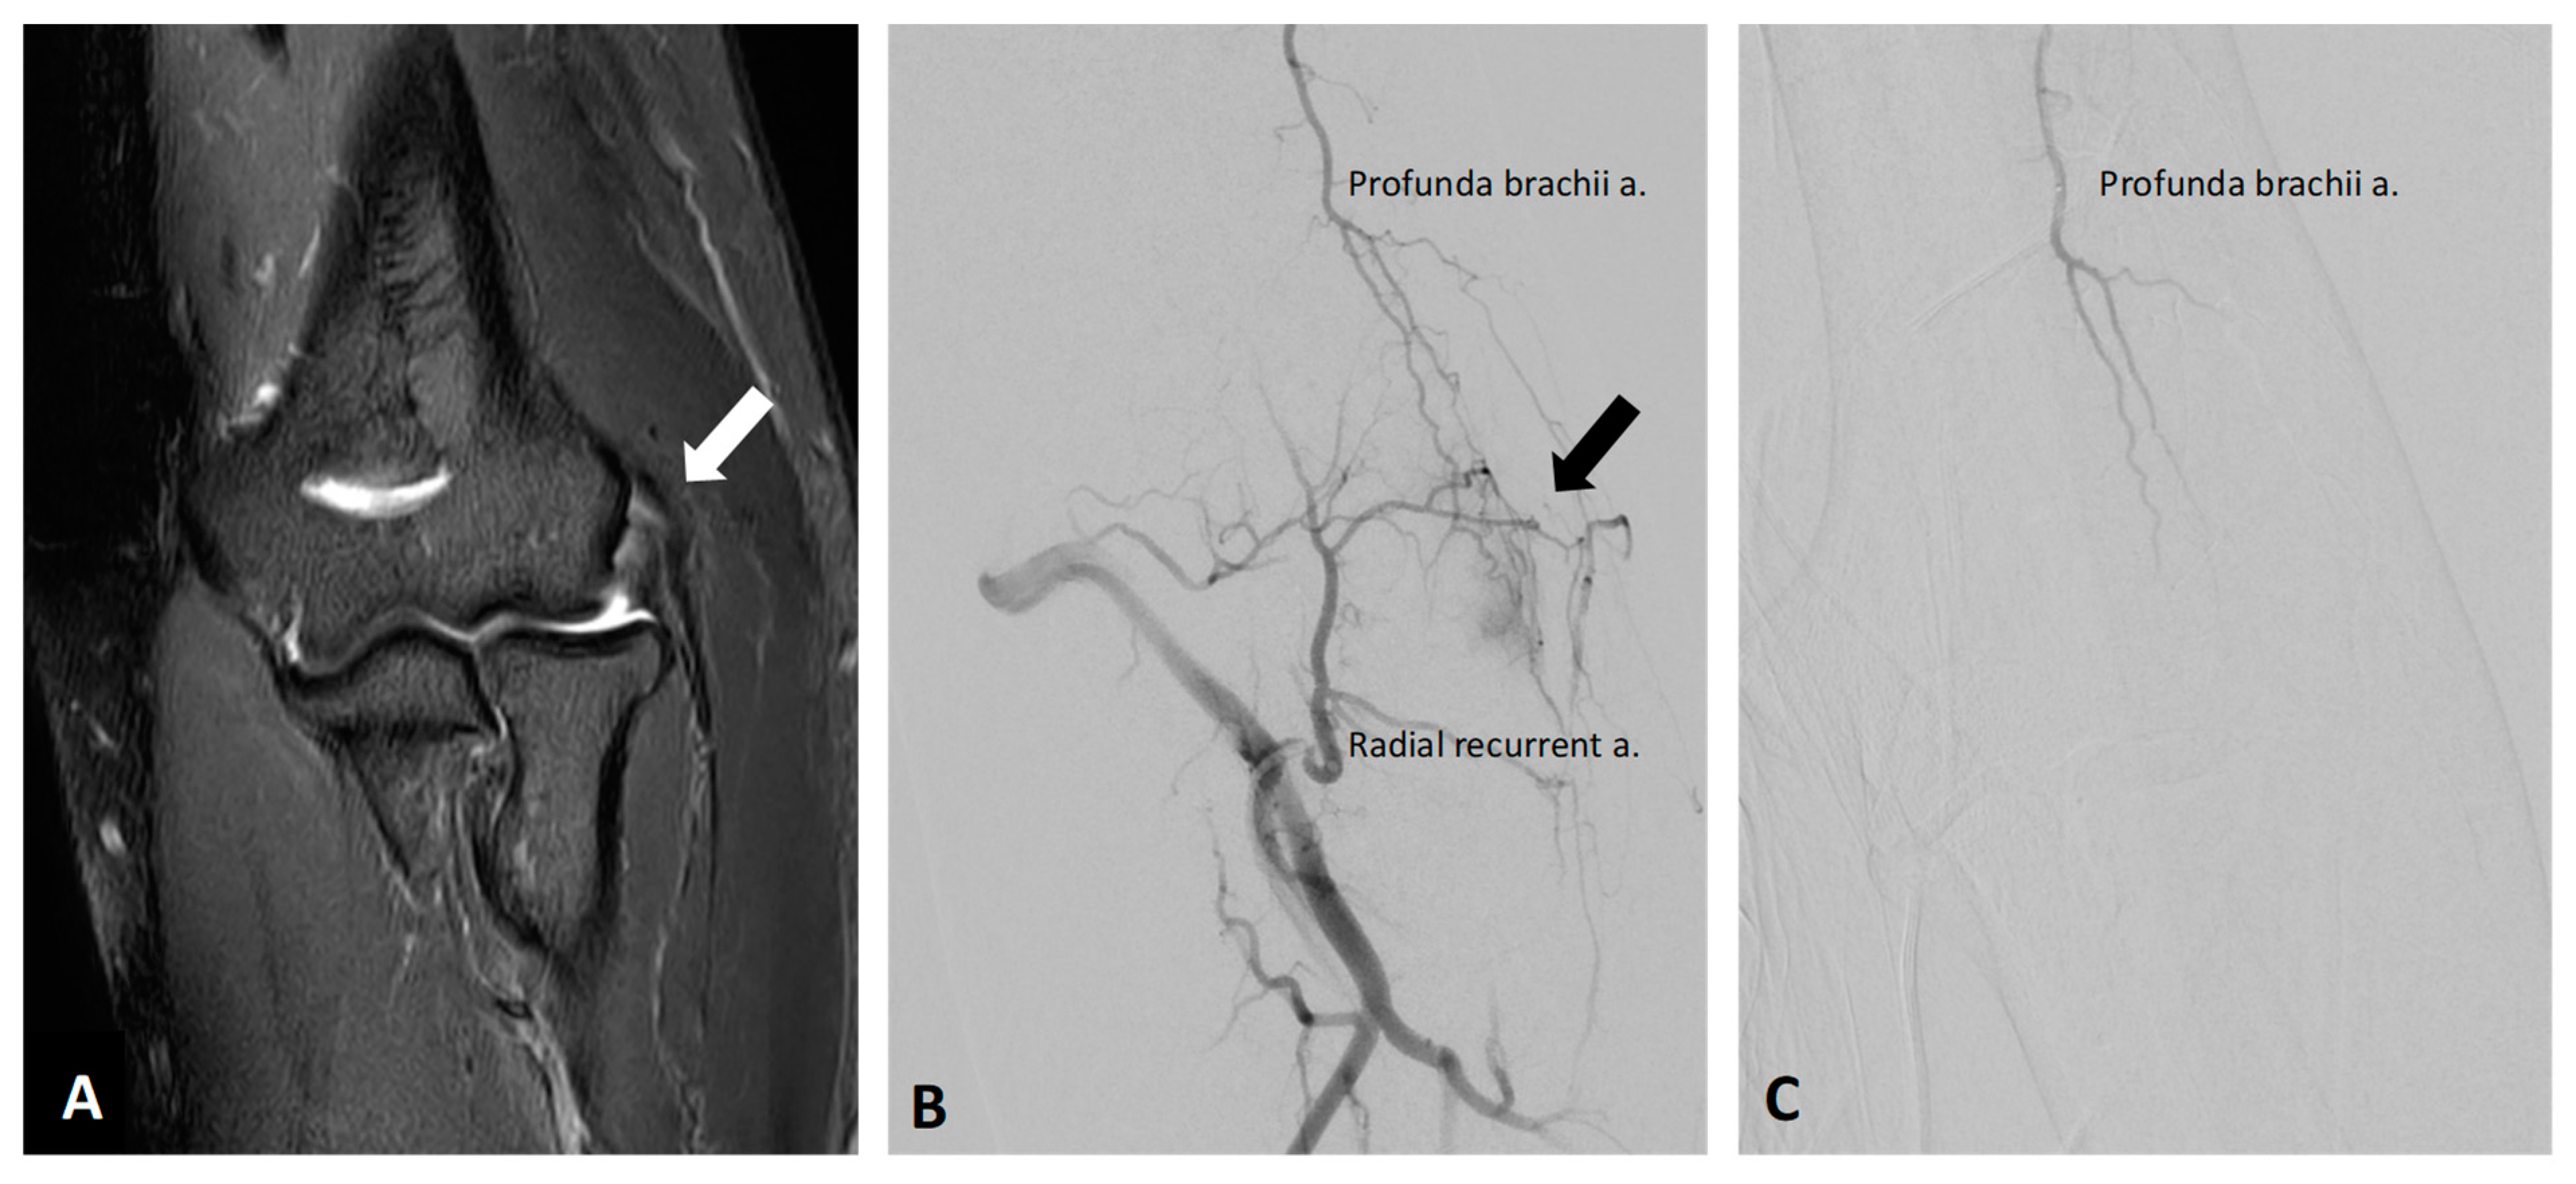

5.2. Lateral Epicondylitis

- Iwamoto, W.; Okuno, Y.; Matsumura, N.; Kaneko, T.; Ikegami, H. Transcatheter arterial embolization of abnormal vessels as a treatment for lateral epicondylitis refractory to conservative treatment: A pilot study with a 2-year follow-up. J. Shoulder Elb. Surg. 2017, 26, 1335–1341. [Google Scholar] [CrossRef]